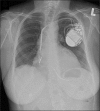

Pneumopericardium after attempted left ventricular lead insertion